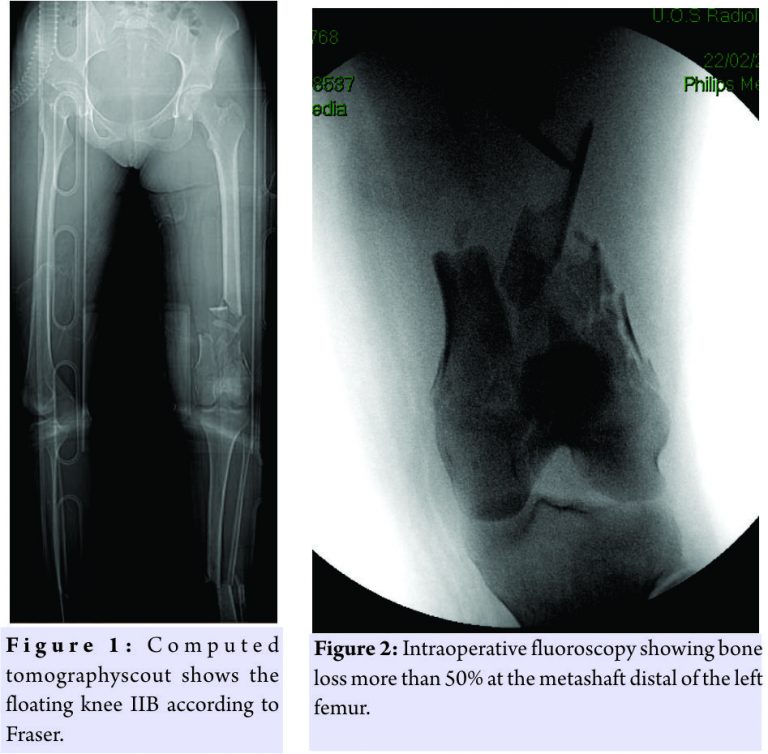

At 4:30 am, a 23-year-old patient arrived at our drug enforcement administration, after a high kinetic energy car accident (car against the wall) in orotracheal intubation with a Glasgow coma scale (GCS) of 11/15, mangled extremity severity score 4 points for the femur, and 3 points for the leg, and an injury severity score of 24 points:oderate concussion, moderate splenic ulcerations, supra-intercondylar fracture of the femur (3.3-C1 according to AO) left exposed Gustilo Anderson (GA) IIIB and bone loss of the metaphyseal area >50% and shaft fracture(Fig.1 and 2) with a third fragment (4.2-B2 according to AO) exposed GA 3B(Fig.1).

The patient was treated in emergency with a bridge femorotibial external fixator after extensive cleaning and debridement of open fractures(Fig.3a and b). After stabilization, the wounds were covered with iodine-impregnated incision drape (Ioban). During the damage control’s operations, a fragment of 8 cm × 3 cm × 4cm of bone substance corticospongiosa was found in the left sock. The fragment was immersed in a solution of cefuroxime, gentamicin, and metronidazole and maintained at a temperature of −3°C until 2h before the intervention because it was irradiated with a dose of 25kGy. The 4days, we removed the antibiotated chains and the Ioban cover which were replaced with vacuum therapy. The patient never had fever over 38°Cduring his 10 days in intensive care and in the ward. The delayed risk of tibial consolidation was equal to 8 of 10 according to A.R.R.C.O. As regards the femur, the risk of non-union of the fracture of the femur of 51 points according to the non-union scoring system(N.U.S.S)